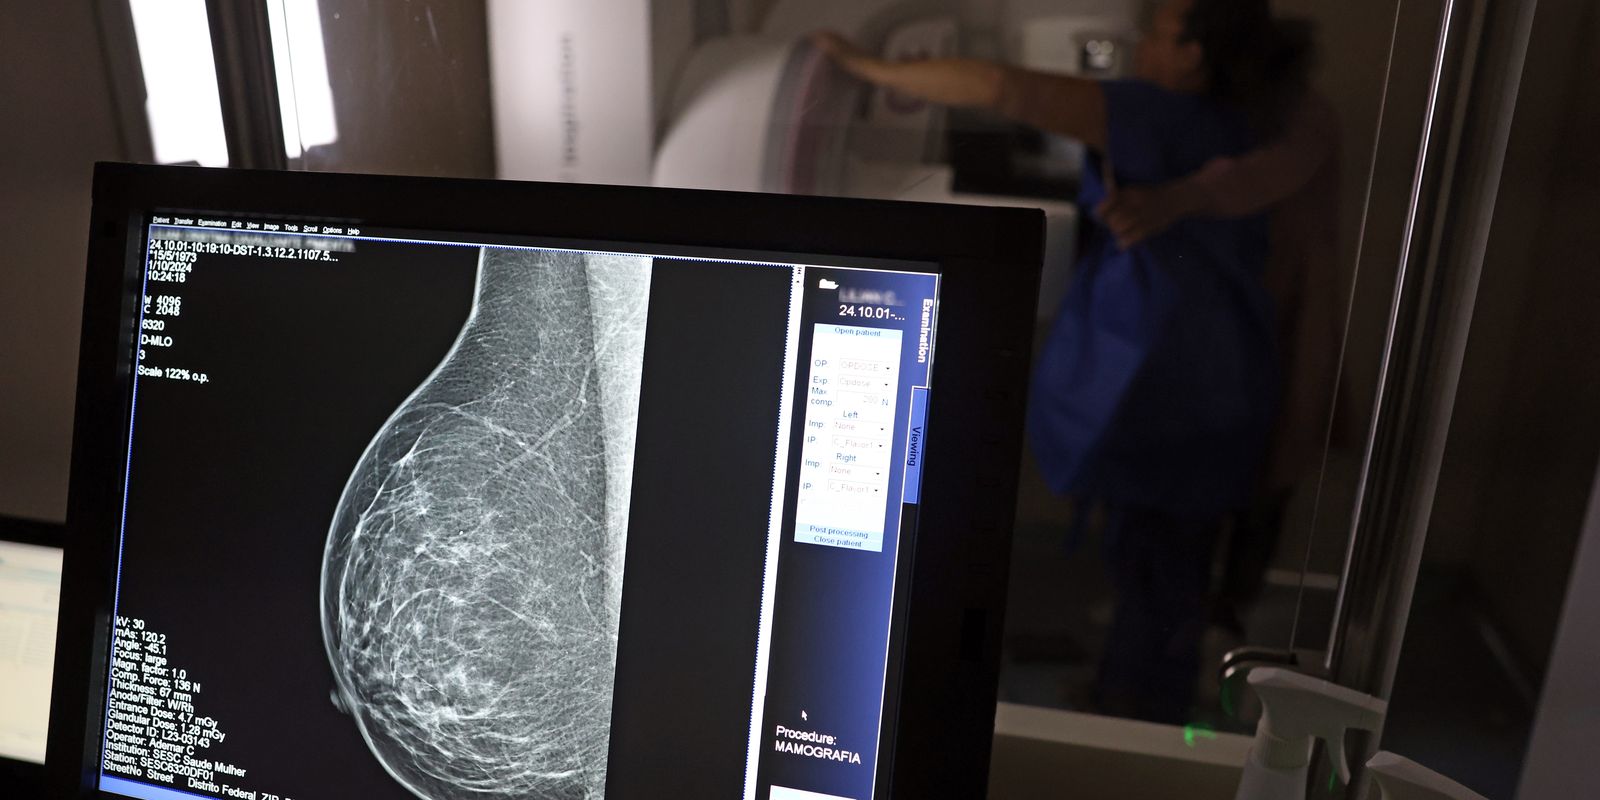

Uma nova lei, publicada nesta segunda-feira (6), reforça o direito do trabalhador com contrato via Consolidação das Leis do Trabalho (CLT) de se afastar até três dias por ano para realizar exames preventivos de câncer, em desconto salarial.

O direito já estava incluído na CLT desde 2018. A partir de agora, as empresas passam a ser obrigadas a divulgar essa informação, além de outras relacionadas a campanhas oficiais de vacinação contra o HPV e sobre o acesso a serviços de diagnósticos de cânceres de mama, próstata e de colo do útero.

O texto estende o uso das folgas também para a realização de exames preventivos do HPV, além dos de câncer que já estavam previstos na legislação anterior. A a Lei 15.377 foi sancionada pelo presidente Luiz Inácio Lula da Silva, e publicada na edição do Diário Oficial da União (DOU).